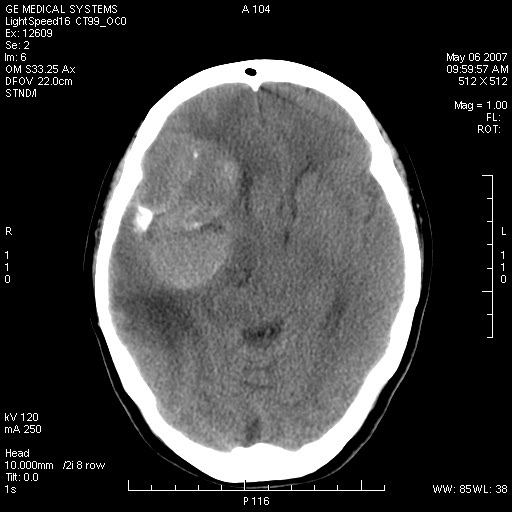

女,60岁,头痛6~7天。

右颞叶巨大高低混杂密度肿块,病灶内可见多发条块状钙化影,占位效应明显,中线结构显著左偏,肿块周围水肿明显,临近颅骨吸收变薄,边缘光整,考虑1少枝胶质瘤2脑膜瘤3转移瘤4室管膜瘤5淋巴瘤6三叉神经瘤(多多益善)合并镰下疝

右颞叶分叶状稍高密度灶,占位效应明显,外周见水肿带,其内见点条样高密度钙化灶,临近颅骨变薄,考虑:脑膜瘤,少突胶质瘤。

右颞叶混杂密度,累及右额叶。其内可见条片状钙化及斑片状略高密度,周围少量水肿,右颞骨吸收变薄,中线结构左移。考虑1少突胶质瘤。2脑膜瘤。合并瘤卒中。建议增强扫描。

右额、颞叶巨大高低混杂密度肿块,病灶内可见多发条块状钙化影,占位效应明显,中线结构显著左偏,肿块周围水肿明显,临近颅骨吸收变薄,边缘光整。

考虑:1、少枝胶质瘤;

2、脑膜瘤?

3、镰下疝;

4、建议增强扫描进一步检查。